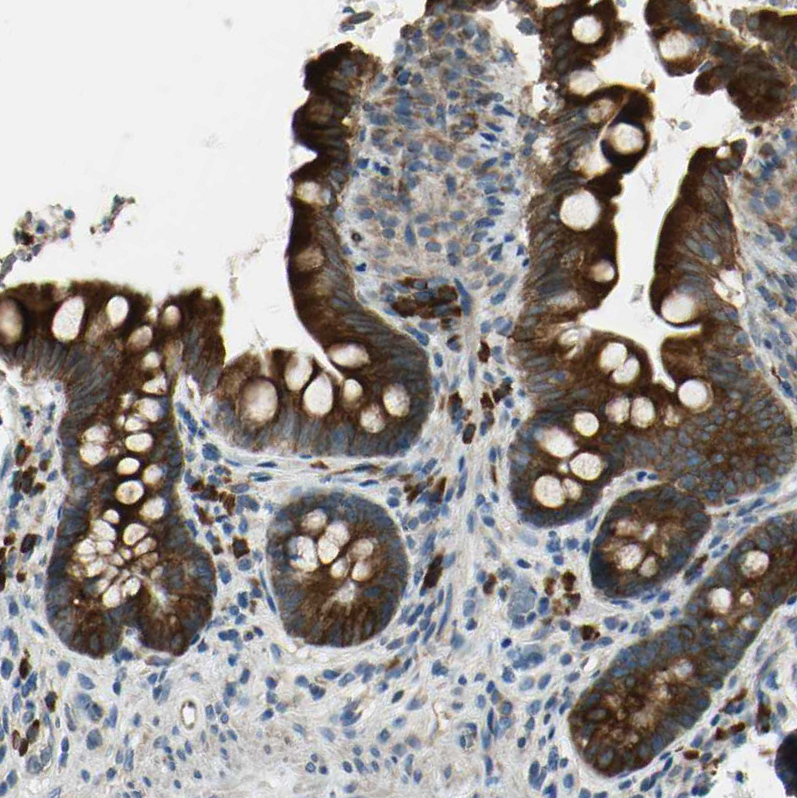

Immunohistochemical staining of human pancreas shows strong cytoplasmic positivity in exocrine glandular cells.